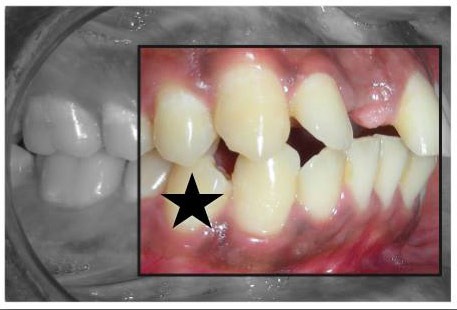

| Front teeth when excessively forwards are prone to trauma and at times, complete loss. |

| This medical student and an aspiring Doc lived through his teens with a removable flipper to hide the missing tooth. |